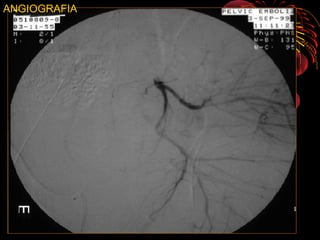

ANGIOGRAFIA

• Angiografía :evidencia de hematom retroperitoneal

y perdida de mas de 4 unidades de GR

RADIOLOGÍA • LA IMAGENOLOGIANO DEBE RETRASAR MANEJO INICIAL • TIPO DE IMÁGENES ESTA DADO POR MECANISMO, GRAVEDAD Y CAPACIDAD DEL CENTRO • PARTIR DE UNA RX. A.P. PARA DIAGNÓSTICO • COMPLEMENTARIS : 60°”E”-30°”S” Y OBLICUAS • TAC : Herramienta de elección en fx. de pelvis permite evaluar el compromiso óseo, fragmentario, grados de desplazamiento, compromisos abdominopélvicos y diferenciar hematomas retro e intra abdominales • Uretrocistograma en caso de hematuria franca • Angiografía :evidencia de hematom retroperitoneal y perdida de mas de 4 unidades de GR